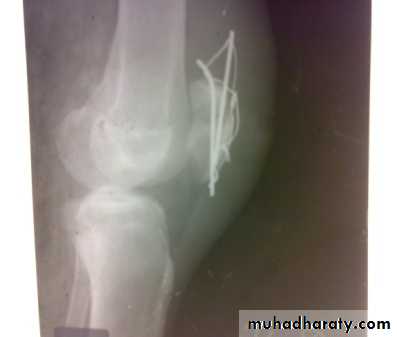

Tibial plateau fractures:Direct blow or fall from height may cause fracture of one tibial condyle or both.

Fracture lateral condyle is the commonest named as bumper fracture

caused by a force that abducts the tibia upon femur while the foot is fixed on ground.Patient usually is an adult, the knee joint is swollen, bruises, there is diffuse tenderness and doughy feel of haemarthrosis.

ligaments injuries must be excluded.

Imaging : X-ray

: anteroposterior, lateral & oblique views.

CT -Scan may used to detect amount of depression and comminuation.Tibial plateau fracture

Treatment:

Undisplaced fractures

treated conservatively:Haemarthrosis aspiration and compression bandaging,

above knee cast for one monthsfollowed by functional brace and physiotherapy.

For displaced fracturestreatment is by open reduction and internal fixation with

plate and screws as it is an intra articular fracture.fixation of tibial plateau fracture